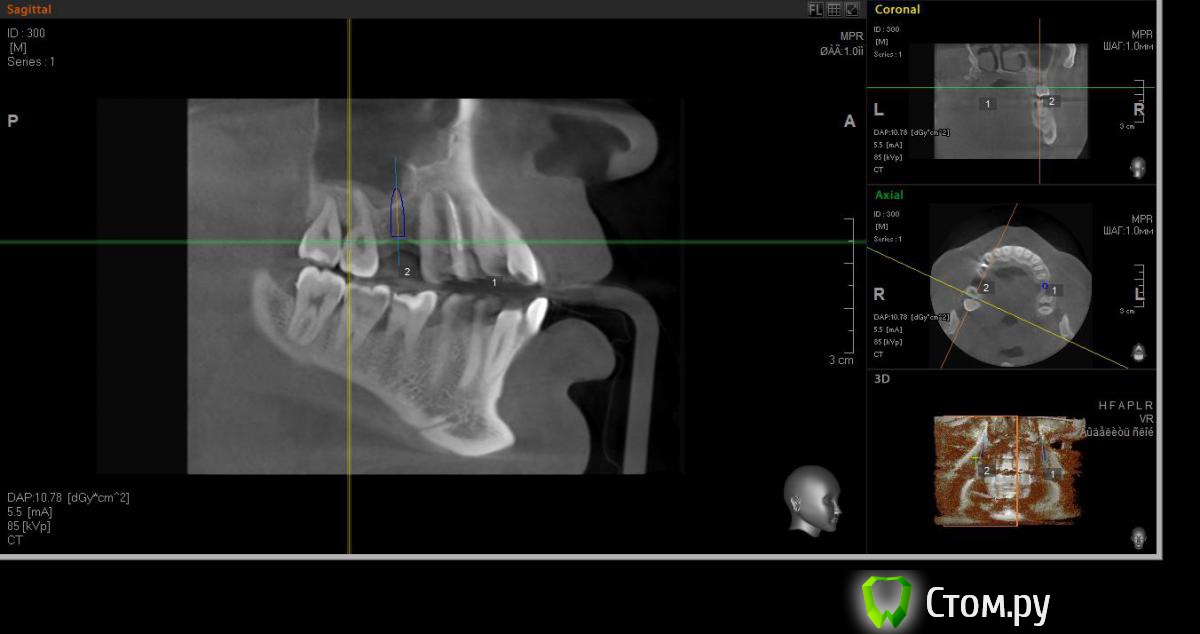

faity Опубликовано 18 мая, 2014 Автор Поделиться Опубликовано 18 мая, 2014 хочу вот так сделать, на 1.6 мягкий лифт, в обл 2.6 не лезтьвинты Ankylos 1.6- 4,5/11 2.6- 3,5/9,5кости в области 1.6- 7,5мм, должно хватить для закрытого, открытый пациент не потянет по финансам.какие мысли? Ссылка на комментарий

red_butler Опубликовано 19 мая, 2014 Поделиться Опубликовано 19 мая, 2014 Я бы не планировал хирургию исходя из финансовых пожеланий пациента, и 1.6 вел бы с открытым синусом. Представьте что при закрытом порвали мембрану, открытый придется делать, и за свой счет. Винт в позицию 1.6 поставил бы меньшего диаметра Ссылка на комментарий

faity Опубликовано 19 мая, 2014 Автор Поделиться Опубликовано 19 мая, 2014 значит буду открытый делать, и винт на 3,5а по поводу 2.6 предложений никаких? Ссылка на комментарий

faity Опубликовано 19 мая, 2014 Автор Поделиться Опубликовано 19 мая, 2014 Я бы не планировал хирургию исходя из финансовых пожеланий пациента, и 1.6 вел бы с открытым синусом. Представьте что при закрытом порвали мембрану, открытый придется делать, и за свой счет. Винт в позицию 1.6 поставил бы меньшего диаметрапоменял винты на 3,5/11 Ссылка на комментарий

red_butler Опубликовано 19 мая, 2014 Поделиться Опубликовано 19 мая, 2014 (изменено) Не знаю диаметры винтов в этой системе, между 3.5 и 4.5 Промежуточного нет?А 2.6 без синуса и диаметр больше Изменено 19 мая, 2014 пользователем red_butler Ссылка на комментарий

faity Опубликовано 19 мая, 2014 Автор Поделиться Опубликовано 19 мая, 2014 Не знаю диаметры винтов в этой системе, между 3.5 и 4.5 Промежуточного нет?А 2.6 без синуса и диаметр большепромежуточных к сожалению нета 2,6 больше не получитсяэто при ныненшнем радиусе и положении, если делать больше винт, то больше углублять, а тогда в синус провалюсь Ссылка на комментарий